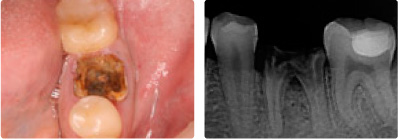

インプラント

治療前

治療後